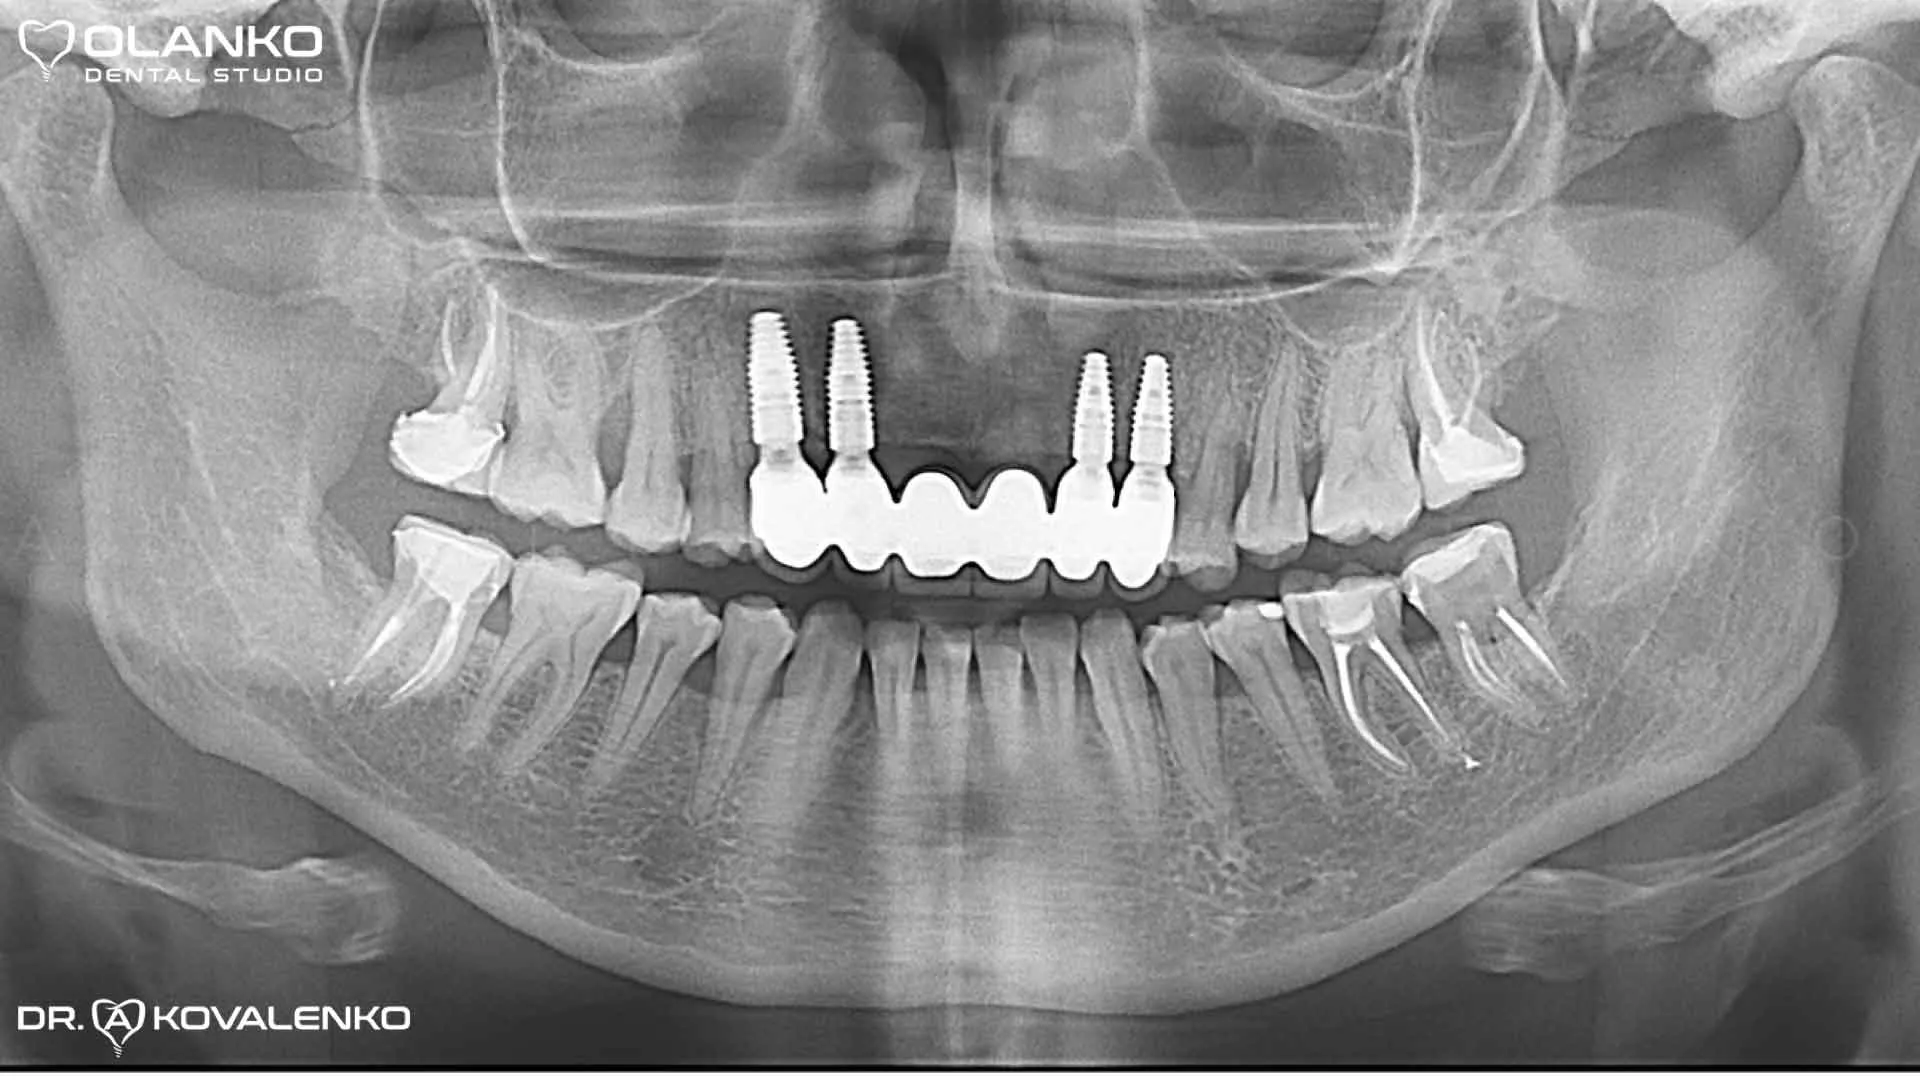

Контрольний панорамний рентген знімок після закінчення протезування на імплантатах

Видалили 5  зубів з одномоментною імплантацією, кістковою та ясеневою пластикою. Встановлено чотири зубних імплантати Straumann Roxolid SLA. Через 4 місяці проведено протезування, на імплантати встановлений безметаловий мостовидний протез з діоксиду цирконію.